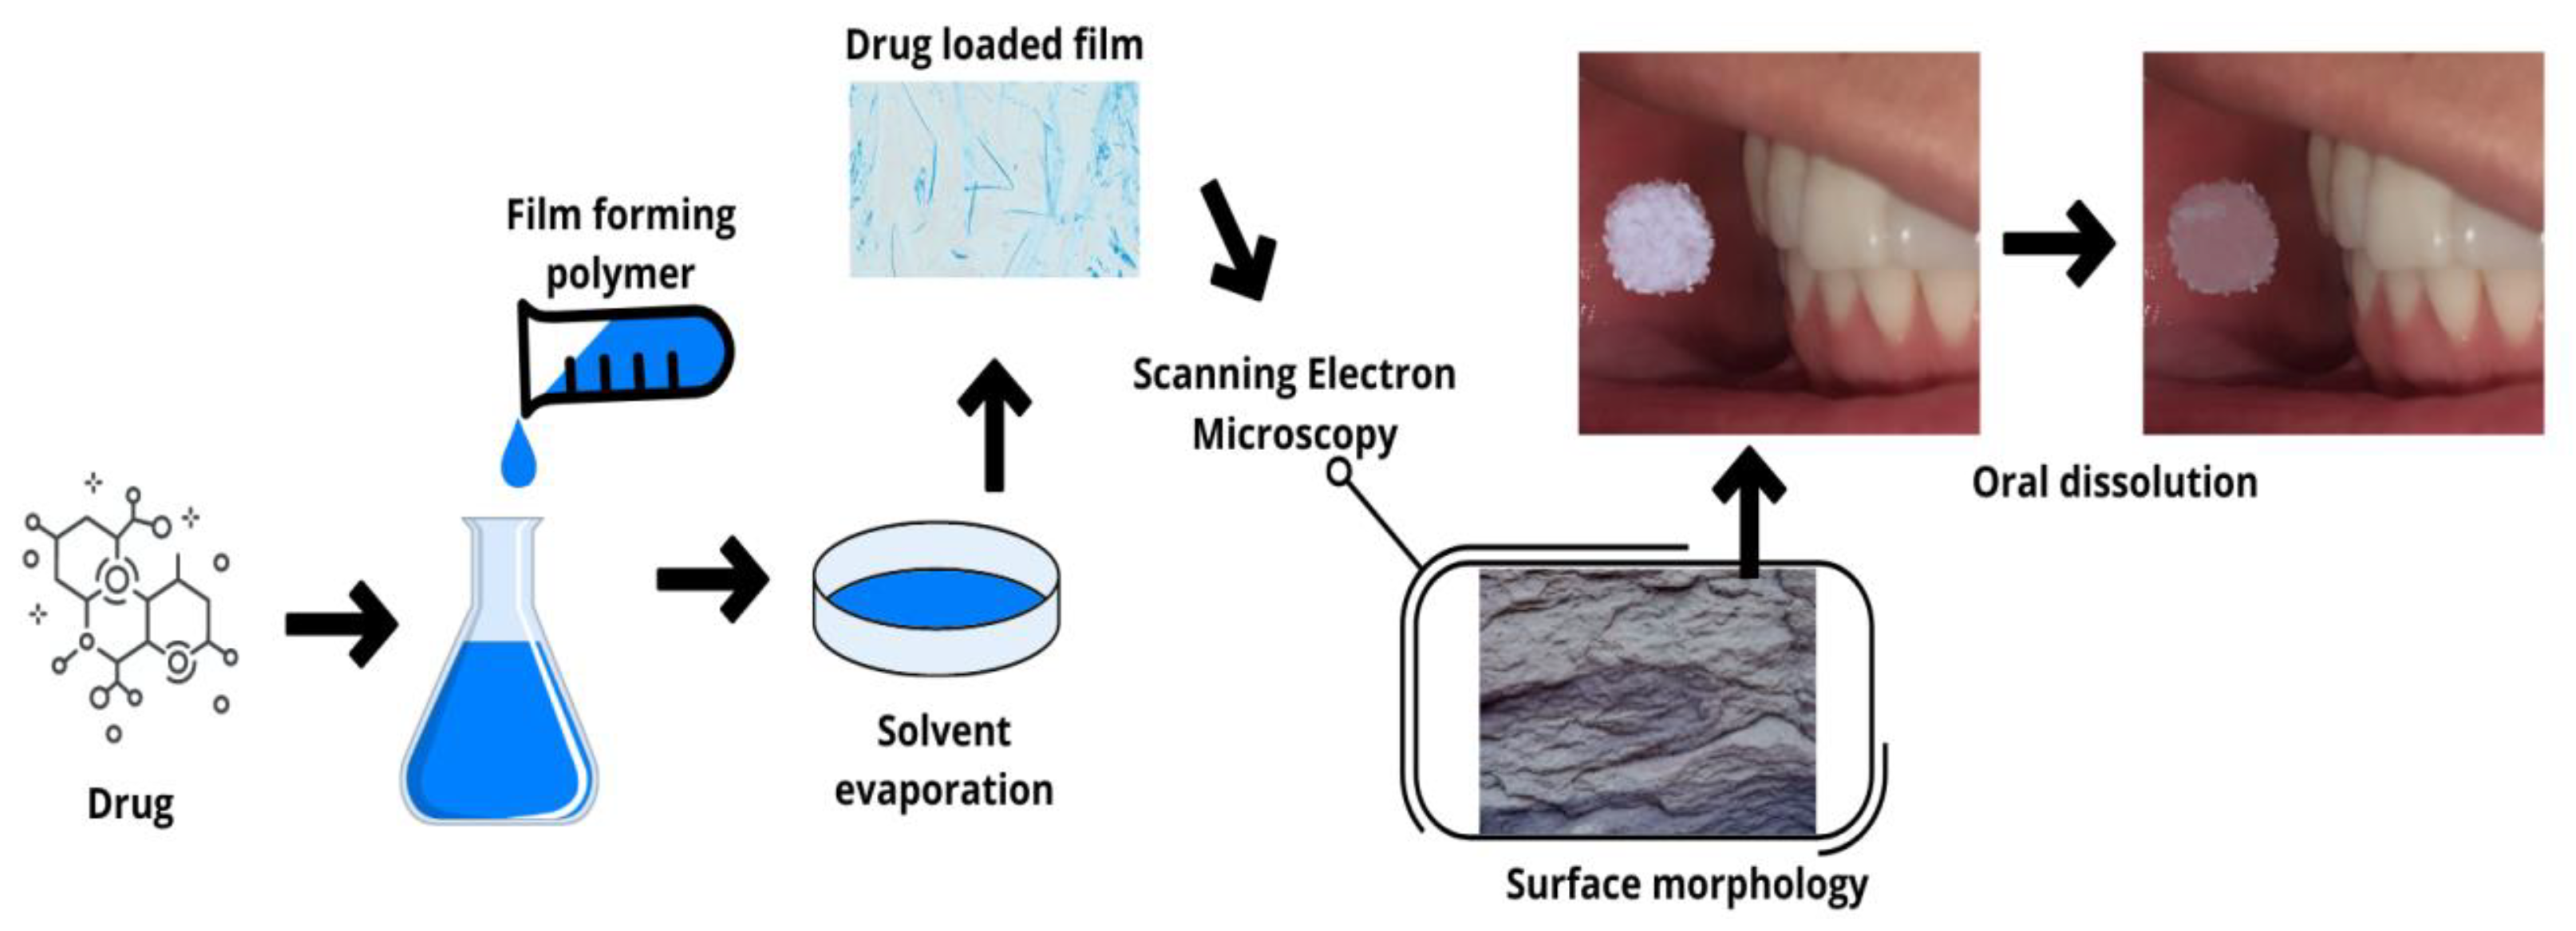

2.1. Fast-Dissolving Films (Oro-Dissolving)

5.1. Solvent Casting Method